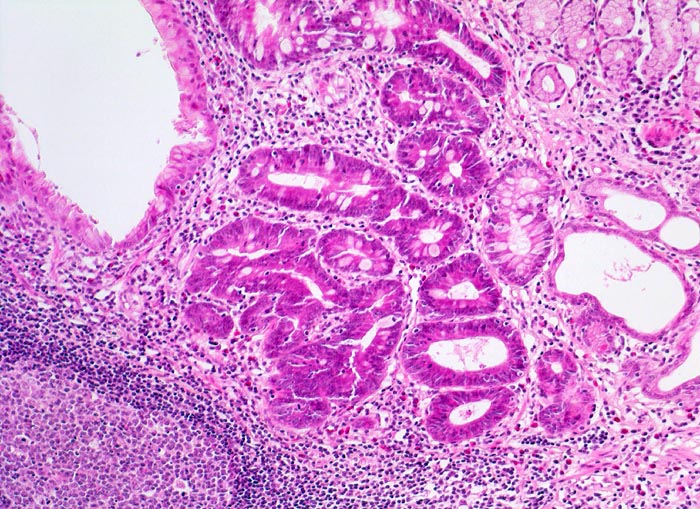

AP/ Chronisch aktive Helicobactergastritis mit intestinaler Metaplasie

Chronisch aktive Helicobactergastritis mit intestinaler Metaplasie

Das Unterrichtspräparat zeigt eine Helicobacter-Gastritis mit intestinaler Metaplasie. Histologisch ist die Typ B Gastritis charakterisiert durch eine chronische (Plasmazellen und Lymphozyten) und aktive (neutrophile Granulozyten) Entzündung. Das Ausmass der chronischen Entzündung und die Entzündungsaktivität werden gemäss Sydney Klassifikation in drei Schweregrade unterteilt (z.B. mässiggradige chronische, stark aktive Gastritis). Fakultativ können Lymphfollikel, eine intestinale Metaplasie mit/ohne Dysplasie und/oder Drüsenatrophie hinzukommen. Die Erreger (Helicobacter pylori) kolonisieren den protektiven Schleimfilm auf der Magenmukosa (> 3330) (> 9968) und sind dort mittels Spezialfärbung (Giemsa C) mikroskopisch nachweisbar. Unmittelbar im Bereich der intestinalen Metaplasie sind aufgrund des veränderten Milieus meist keine Bakterien nachweisbar. Unter Einnahme von Säurehemmern oder Antibiotika verringert sich die Sensitivität des Bakteriennachweises in der Biopsie aufgrund der schnellen Reduktion der Bakterienanzahl ebenfalls. Nach erfolgreicher Eradikation verschwindet in der Regel die aktive Entzündung innert Wochen. Chronische Entzündung und Lymphfollikel bleiben jedoch länger nachweisbar und geben einen Hinweis auf eine abgelaufene Helicobactergastritis.

Die intestinale Metaplasie also der Ersatz des ortsständigen Epithels durch ein differenziertes anderes Gewebe (Ersatz des Magenepithels durch Dünndarm- oder Dickdarm-ähnliches Epithel) ist in Magenbiopsien ein häufiger Befund. Sie ist Folge einer chronischen Magenschleimhautentzündung unabhängig von deren Ätiologie. Man findet sie besonders häufig in Mägen mit Ulcus ventriculi und in enger Assoziation mit dem Magenkarzinom. Im metaplastischen Gewebe kann sich eine Dysplasie entwickeln. In einer niederländischen Kohortenstudie wurde das 5-Jahres-Risiko für die Entwicklung eines Magenkarzinoms bei Vorliegen einer atrophen Gastritis mit 0.1%, bei intestinaler Metaplasie mit 0.25%, bei niedrig- bis mittelgradiger Dysplasie mit 0.6% und bei schwerer Dysplasie mit 6% angegeben.

• Vier Magenschleimhautbiopsien (Oberstes: Antrum/Corpusübergang mit intestinaler Metaplasie, zweitoberstes und unterstes: Antrumschleimhaut mit intestinaler Metaplasie, zweitunterstes: Corpusschleimhaut mit intramukosalem Lymphfollikel ohne Metaplasie).

• Schwere chronische (dichtes lymphoplasmazelluläres Entzündungsinfiltrat in der Lamina propria), stark aktive (neutrophile Granulozyten in der Lamina propria und im Epithel mit Ausbildung von Mikroabszessen) Gastritis.

• Typisch für Helicobactergastritis: intramukosale Lymphfollikel

• An der Schleimhautoberfläche sind einzelne blauviolette kommaförmige Helicobacter Bakterien erkennbar. Die Bakterien sind viel besser in der Spezialfärbung Giemsa C erkennbar (zweiter Präparatlink, ebenfalls Prüfungsstoff!!)

• Intestinale Metaplasie der Antrumschleimhaut: Basophile (bläuliche) Drüsenschläuche mit Becherzellen sowie einzelnen Paneth'schen Körnerzellen mit rot granuliertem Zytoplasma im untersten Schleimhautfragment. Die metaplastische Schleimhaut erinnert stark an Kolonschleimhaut.